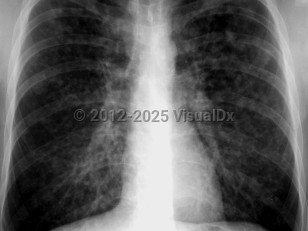

Chest radiograph changes that can be seen include interstitial changes and nodular infiltrates.

Imaging Studies image of Varicella pneumonia - imageId=1909872. Click to open in gallery.  caption: '<span>PA radiograph of a patient with varicella pneumonia showing widespread poorly defined nodules</span>.'

PA radiograph of a patient with varicella pneumonia showing widespread poorly defined nodules.